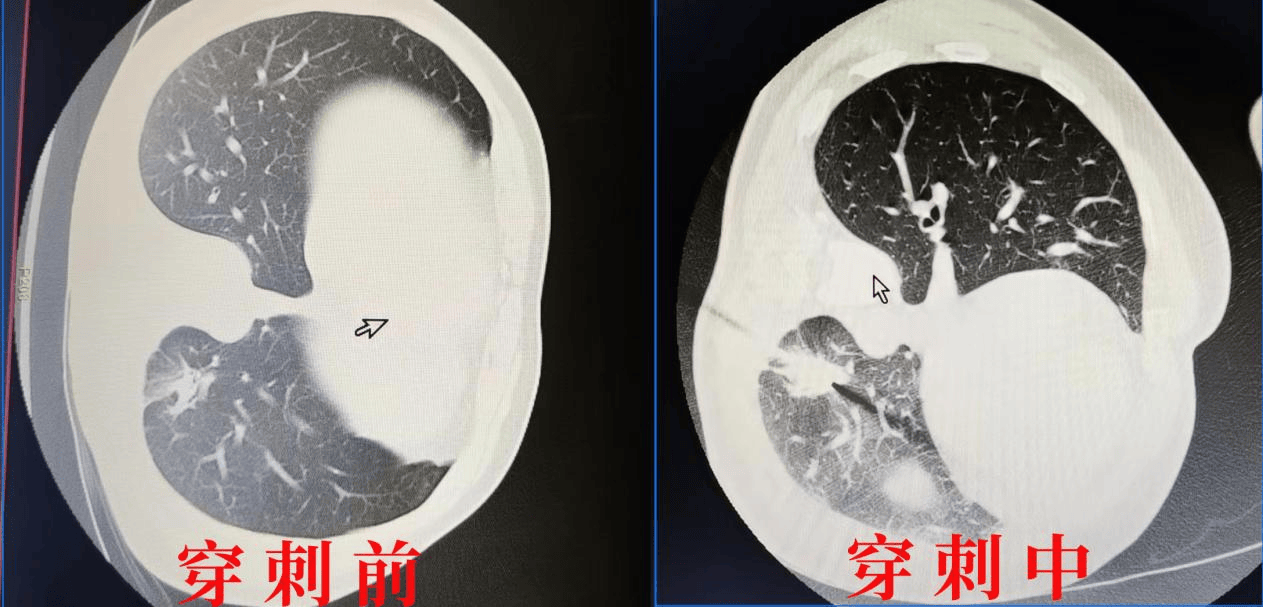

患者为39岁肺癌晚期患者,肺内孤立性病灶有进展趋势。在充分评估患者整体病情结合局部病灶进展的背景下,与患者充分沟通,行CT引导下经皮肺部病损射频消融术。术后患者情况良好,副反应小。

CT引导下射频消融优点是CT空间分辨率及密度分辨率高,可行三维立体成像,能清晰显示肿瘤位置、数量、大小、形态、及其与周围组织结构的毗邻关系,并精确显示射频电极针与肿瘤和周围组织结构的关系。CT引导不受气体及骨骼的影响,无应用死角及盲区,可精准引导全身任何部位肿瘤的消融治疗,同时评价肿瘤消融情况和有无并发症。